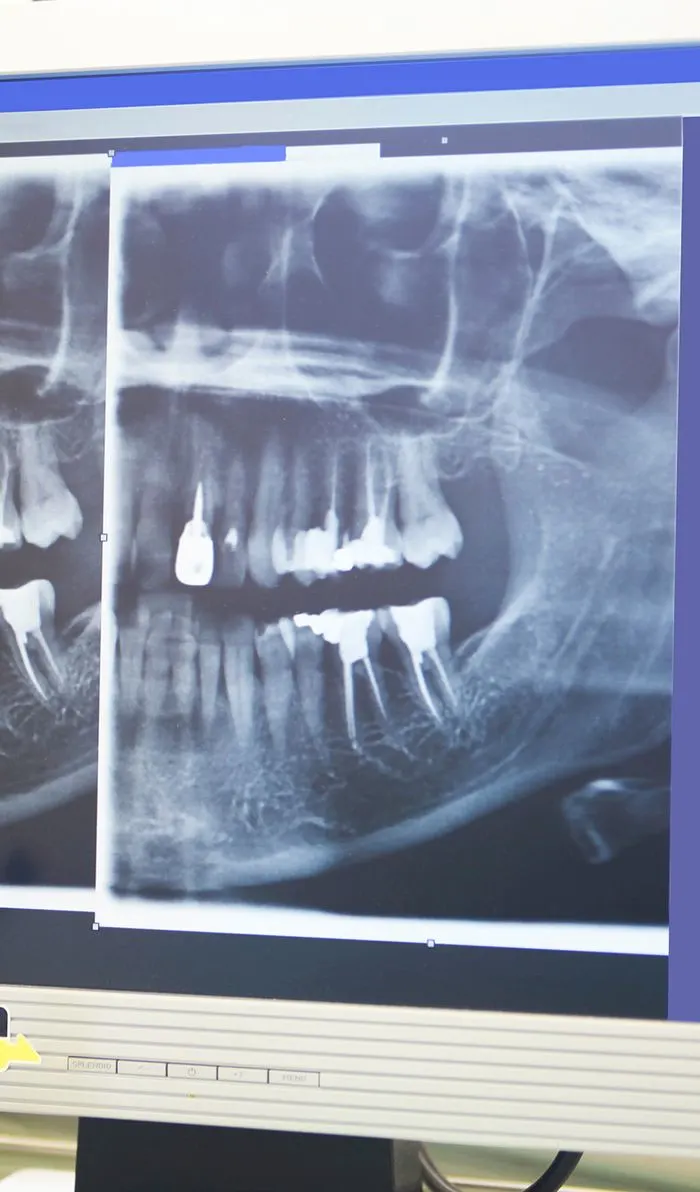

Your dentist will begin with a comprehensive examination of your tooth and x-rays to identify the cause of your dental discomfort. If an infection is present, they'll assess its severity to determine if a root canal is the appropriate treatment option.If root canal therapy is necessary, your dentist will ensure the treatment area is completely numb, including the nerves. Before starting the procedure, they'll discuss various sedation options with you to ensure your comfort throughout the treatment.

Your general dentist may have already taken some recent X-rays of your teeth before your visit with us. To arrive at a diagnosis and recommend treatment, we require specific angles of the tooth that can only be obtained with in-house imaging. We will do our best to obtain the images from your referring dentist and compare them to our own, so that we can review the complete picture with you.